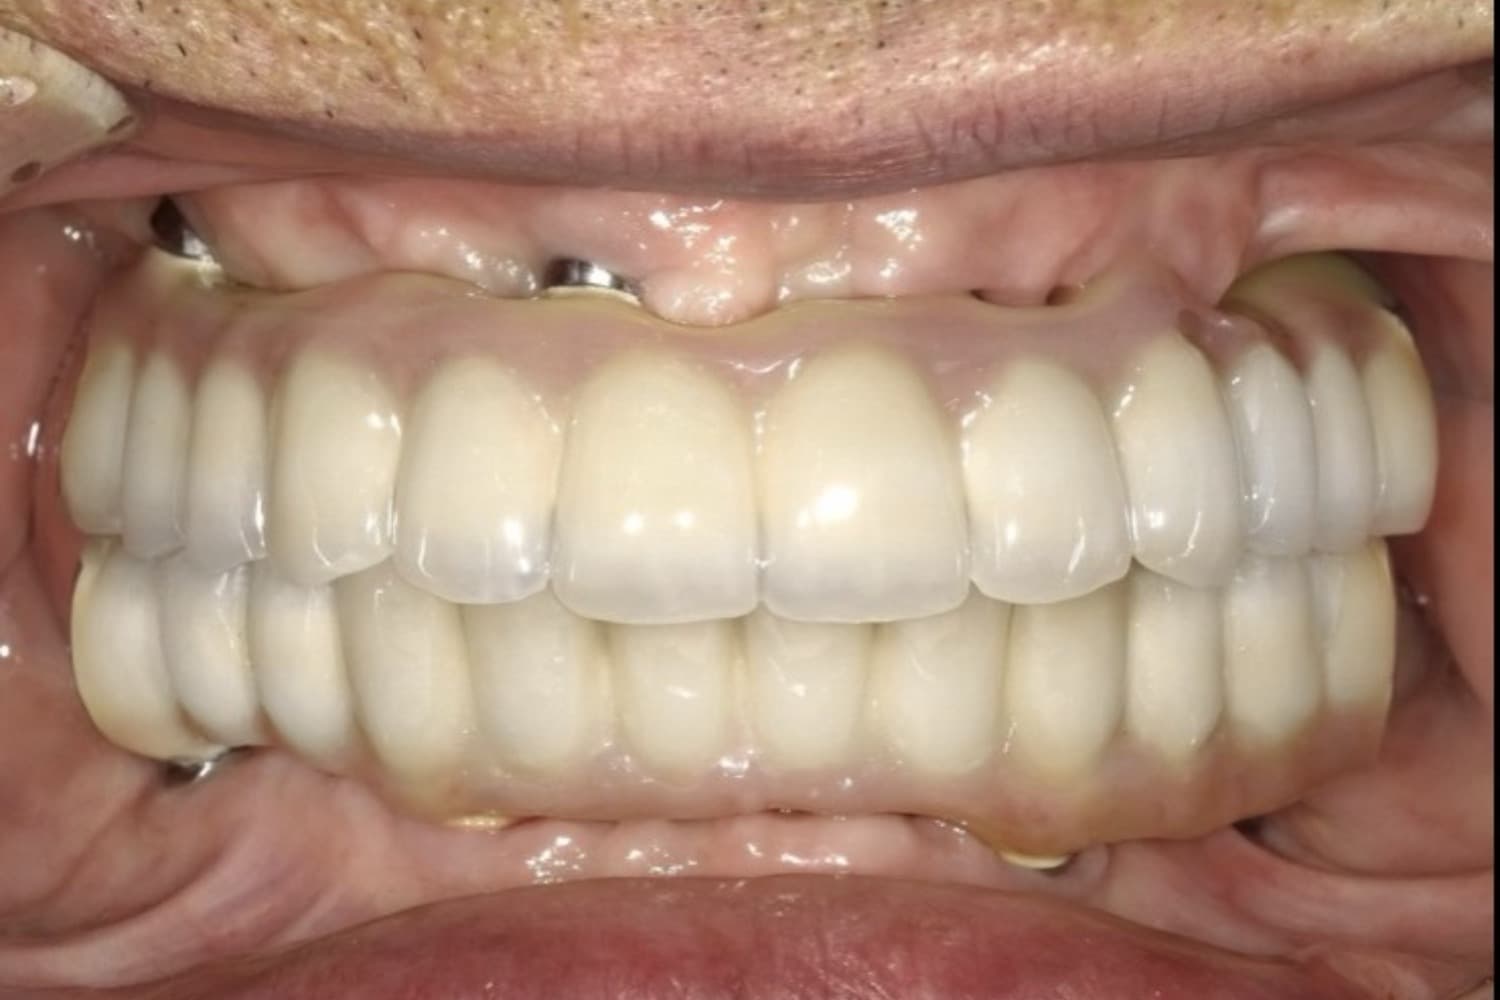

上下のインプラント治療

After

上下の保存できない歯を抜歯して、インプラント治療で咬合機能の回復をおこなう

60代

女性

上下の入れ歯が合わない。しっかり噛めるようになりたい。

8ヵ月

6回~7回

550万円